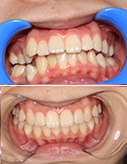

全口氟斑牙修复--瓷贴面